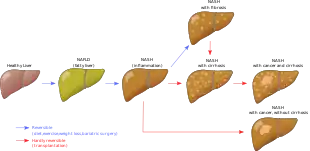

| Stages of metabolic dysfunction–associated steatotic liver disease, progressing from healthy, to steatosis (fat accumulation), inflammation, fibrosis and cirrhosis. | |

Metabolic dysfunction–associated steatotic liver disease (MASLD) is the name adopted in 2023 for the condition previously known as non-alcoholic fatty liver disease (NAFLD).[lower-alpha 1] This condition is diagnosed when there is excessive fat build-up in the liver (hepatic steatosis), and at least one metabolic risk factor.[1][3][4] When there is also moderate alcohol use, the term MetALD is used, and these are differentiated from alcoholic liver disease (ALD) when this is the sole cause of steatotic liver disease.[1][12] The terms non-alcoholic fatty liver (NAFL) and non-alcoholic steatohepatitis (NASH, now MASH) have been used to describe different severities, with the latter indicating the presence of further liver inflammation.[4][5][8] NAFL is less dangerous than NASH and usually does not progress towards it,[4] but this progression may eventually lead to complications such as cirrhosis, liver cancer, liver failure, or cardiovascular disease.[4][13]

An abnormal accumulation of fat in the liver in the absence of secondary causes of fatty liver, such as significant alcohol use, viral hepatitis, or medications that can induce fatty liver, was the definition used for NAFLD.[19] However, the term MASLD accepts there may be other conditions present, but focuses on the metabolic abnormalities contributing to the disorder.[1][12] MASLD encompasses a continuum of liver abnormalities, from metabolic dysfunction–associated steatotic liver (MASL, simple steatosis) to Metabolic dysfunction-associated steatohepatitis (MASH). These diseases begin with fatty accumulation in the liver (hepatic steatosis). A liver can remain fatty without disturbing liver function (MASL), but by various mechanisms and possible insults to the liver, it may also progress into steatohepatitis (MASH), a state in which steatosis is combined with inflammation and sometimes fibrosis.[1] MASH can then lead to complications such as cirrhosis and hepatocellular carcinoma.[3][5][26]

MAFLD and NASH increase the risk of liver cancer. Cirrhosis and liver cancer induced by NAFLD were the second cause of liver transplantation in the US in 2017. Liver cancer develops in NASH in the absence of cirrhosis in 45% in the cases,[116] and people with NASH cirrhosis have an increased risk of liver cancer. The rate of liver cancer associated with NASH increased fourfold between 2002 and 2012 in the US, which is more than any other cause of liver cancer. MAFLD constitutes the third most common risk factor for liver cancer.[117] NAFLD and NASH were found to worsen with cirrhosis in respectively 2–3% and 15–20% of the people over a 10–20 year period.[13] Cirrhosis is found in only about 50% of people with MAFLD and with liver cancer, so that liver cancer and cirrhosis are not always linked.[14]